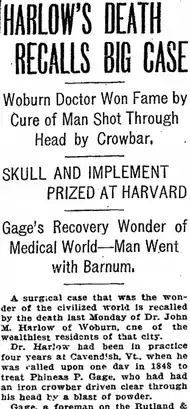

Long known as the "American Crowbar Case"—once termed "the case which more than all others is calculated to excite our wonder, impair the value of prognosis, and even to subvert our physiological doctrines" [2]—Phineas Gage influenced 19th-century discussion about the mind and brain, particularly debate on cerebral localization,

Barker notes that Harlow's original 1848 report of Gage's survival and recovery "was widely disbelieved, for obvious reasons" [B]: 676 and Harlow, recalling this early skepticism in his 1868 retrospective, invoked the biblical story of Doubting Thomas:[L1]: 178

The case occurred nearly twenty years ago, in an obscure country town ..., was attended and reported by an obscure country physician, and was received by the Metropolitan Doctors with several grains of caution, insomuch that many utterly refused to believe that the man had risen, until they had thrust their fingers into the hole [in] his head, and even then they required of the Country Doctor attested statements, from clergymen and lawyers, before they could or would believe—many eminent surgeons regarding such an occurrence as a physiological impossibility, the appearances presented by the subject being variously explained away.

"A distinguished Professor of Surgery in a distant city", Harlow continued, had even dismissed Gage as a "Yankee invention".[H]: 3,18

According to the Boston Medical and Surgical Journal (1869) it was the 1850 report on Gage by Bigelow—Harvard's Professor of Surgery and "a majestic and authoritative figure on the medical scene of those times" [27]—that "finally succeeded in forcing [the case's] authenticity upon the credence of the profession ... as could hardly have been done by any one in whose sagacity and surgical knowledge his confrères had any less confidence".[36] Noting that, "The leading feature of this case is its improbability ... This is the sort of accident that happens in the pantomime at the theater, not elsewhere", Bigelow emphasized that though "at first wholly skeptical, I have been personally convinced".[note 17]